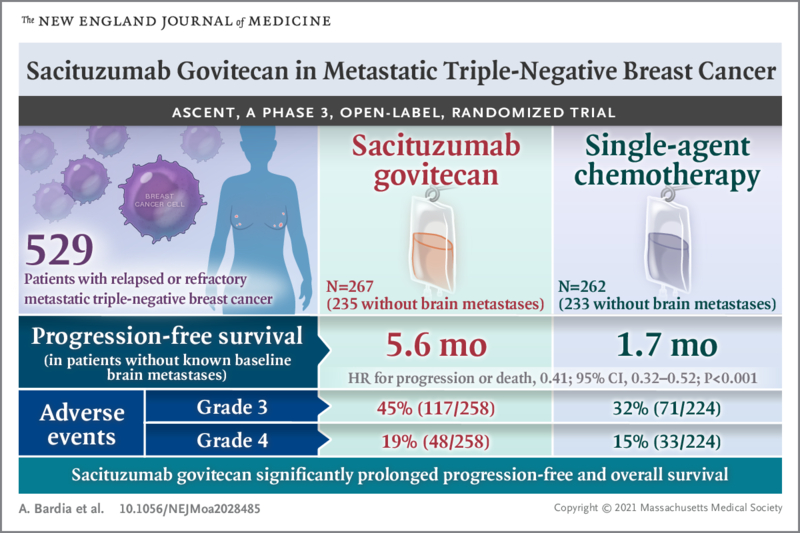

三阴性乳腺癌(TNBC)是指雌激素受体(ER)、孕激素受体(PR)和人表皮生长因子受体2(HER2)均为阴性的一类特殊乳腺癌。由于无相应的治疗靶点,患者具有较差预...

乳腺癌是女性最常见的恶性肿瘤,全球每年新发病例约226万例,占所有女性新发癌症总数的24.5%。尽管化疗及靶向治疗等多种治疗方式提高了乳腺癌的治愈率、延长了乳腺癌...